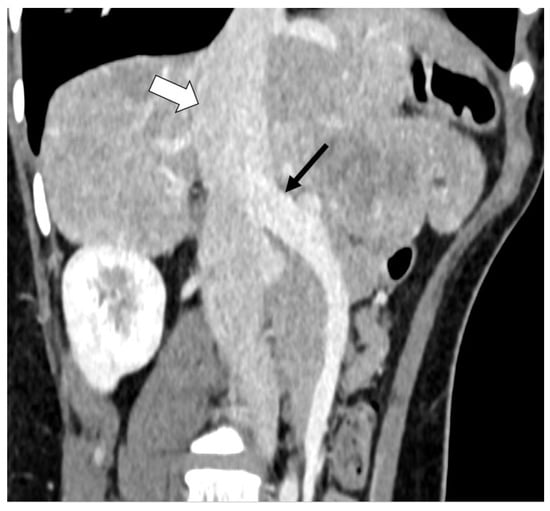

2.1. Case A (Human)

2.2. Case B (Human)